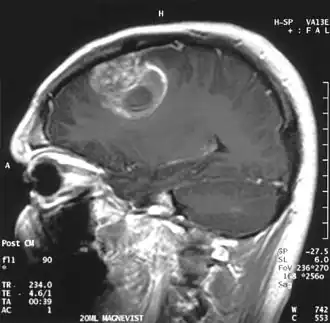

Aan -MRI toont een intracraniële tumor als een massieve laesie die na gebruik van het contrastmiddel meer luminescent kan worden. Er is echter altijd een signaalafwijking in -Magnetic resonance imaging, die de aanwezigheid van neoplasie of vasogeen oedeem aangeeft. Gewoonlijk is verhoogde luminescentie (contrastversterking) indicatief voor een tumor met een hogere graad van maligniteit. Kenmerkend voor glioblastoom is een contrastring, waarbij het lichtgevende deel overeenkomt met het vitale deel van de kwaadaardige tumor en het donkerdere -hypointens gebied dat overeenkomt met weefselnecrose.

Glioblastoom

De meest voorkomende en kwaadaardige gliaceltumoren zijn glioblastomen. Ze bestaan voornamelijk bij volwassenen uit een heterogene massa van slecht gedifferentieerde astrocytoomcellen. Ze komen meestal voor in de hersenhelften, meer zelden in de hersenstam of het ruggenmerg. Behalve in zeer zeldzame gevallen, zoals alle hersentumoren, reiken ze niet verder dan de structuren van het centrale zenuwstelsel.

Glioblastoom kan ontstaan uit een diffuus (II. graad) of een anaplastisch astrocytoom (III. graad) ontwikkelen. In het laatste geval wordt het secundair genoemd. Wanneer het echter optreedt zonder antecedenten of bewijs van eerdere maligniteit, wordt het primair genoemd. Glioblastomen worden behandeld met chirurgie, bestraling en chemotherapie. Ze zijn moeilijk te genezen en er zijn maar weinig gevallen die langer dan drie jaar overleven.